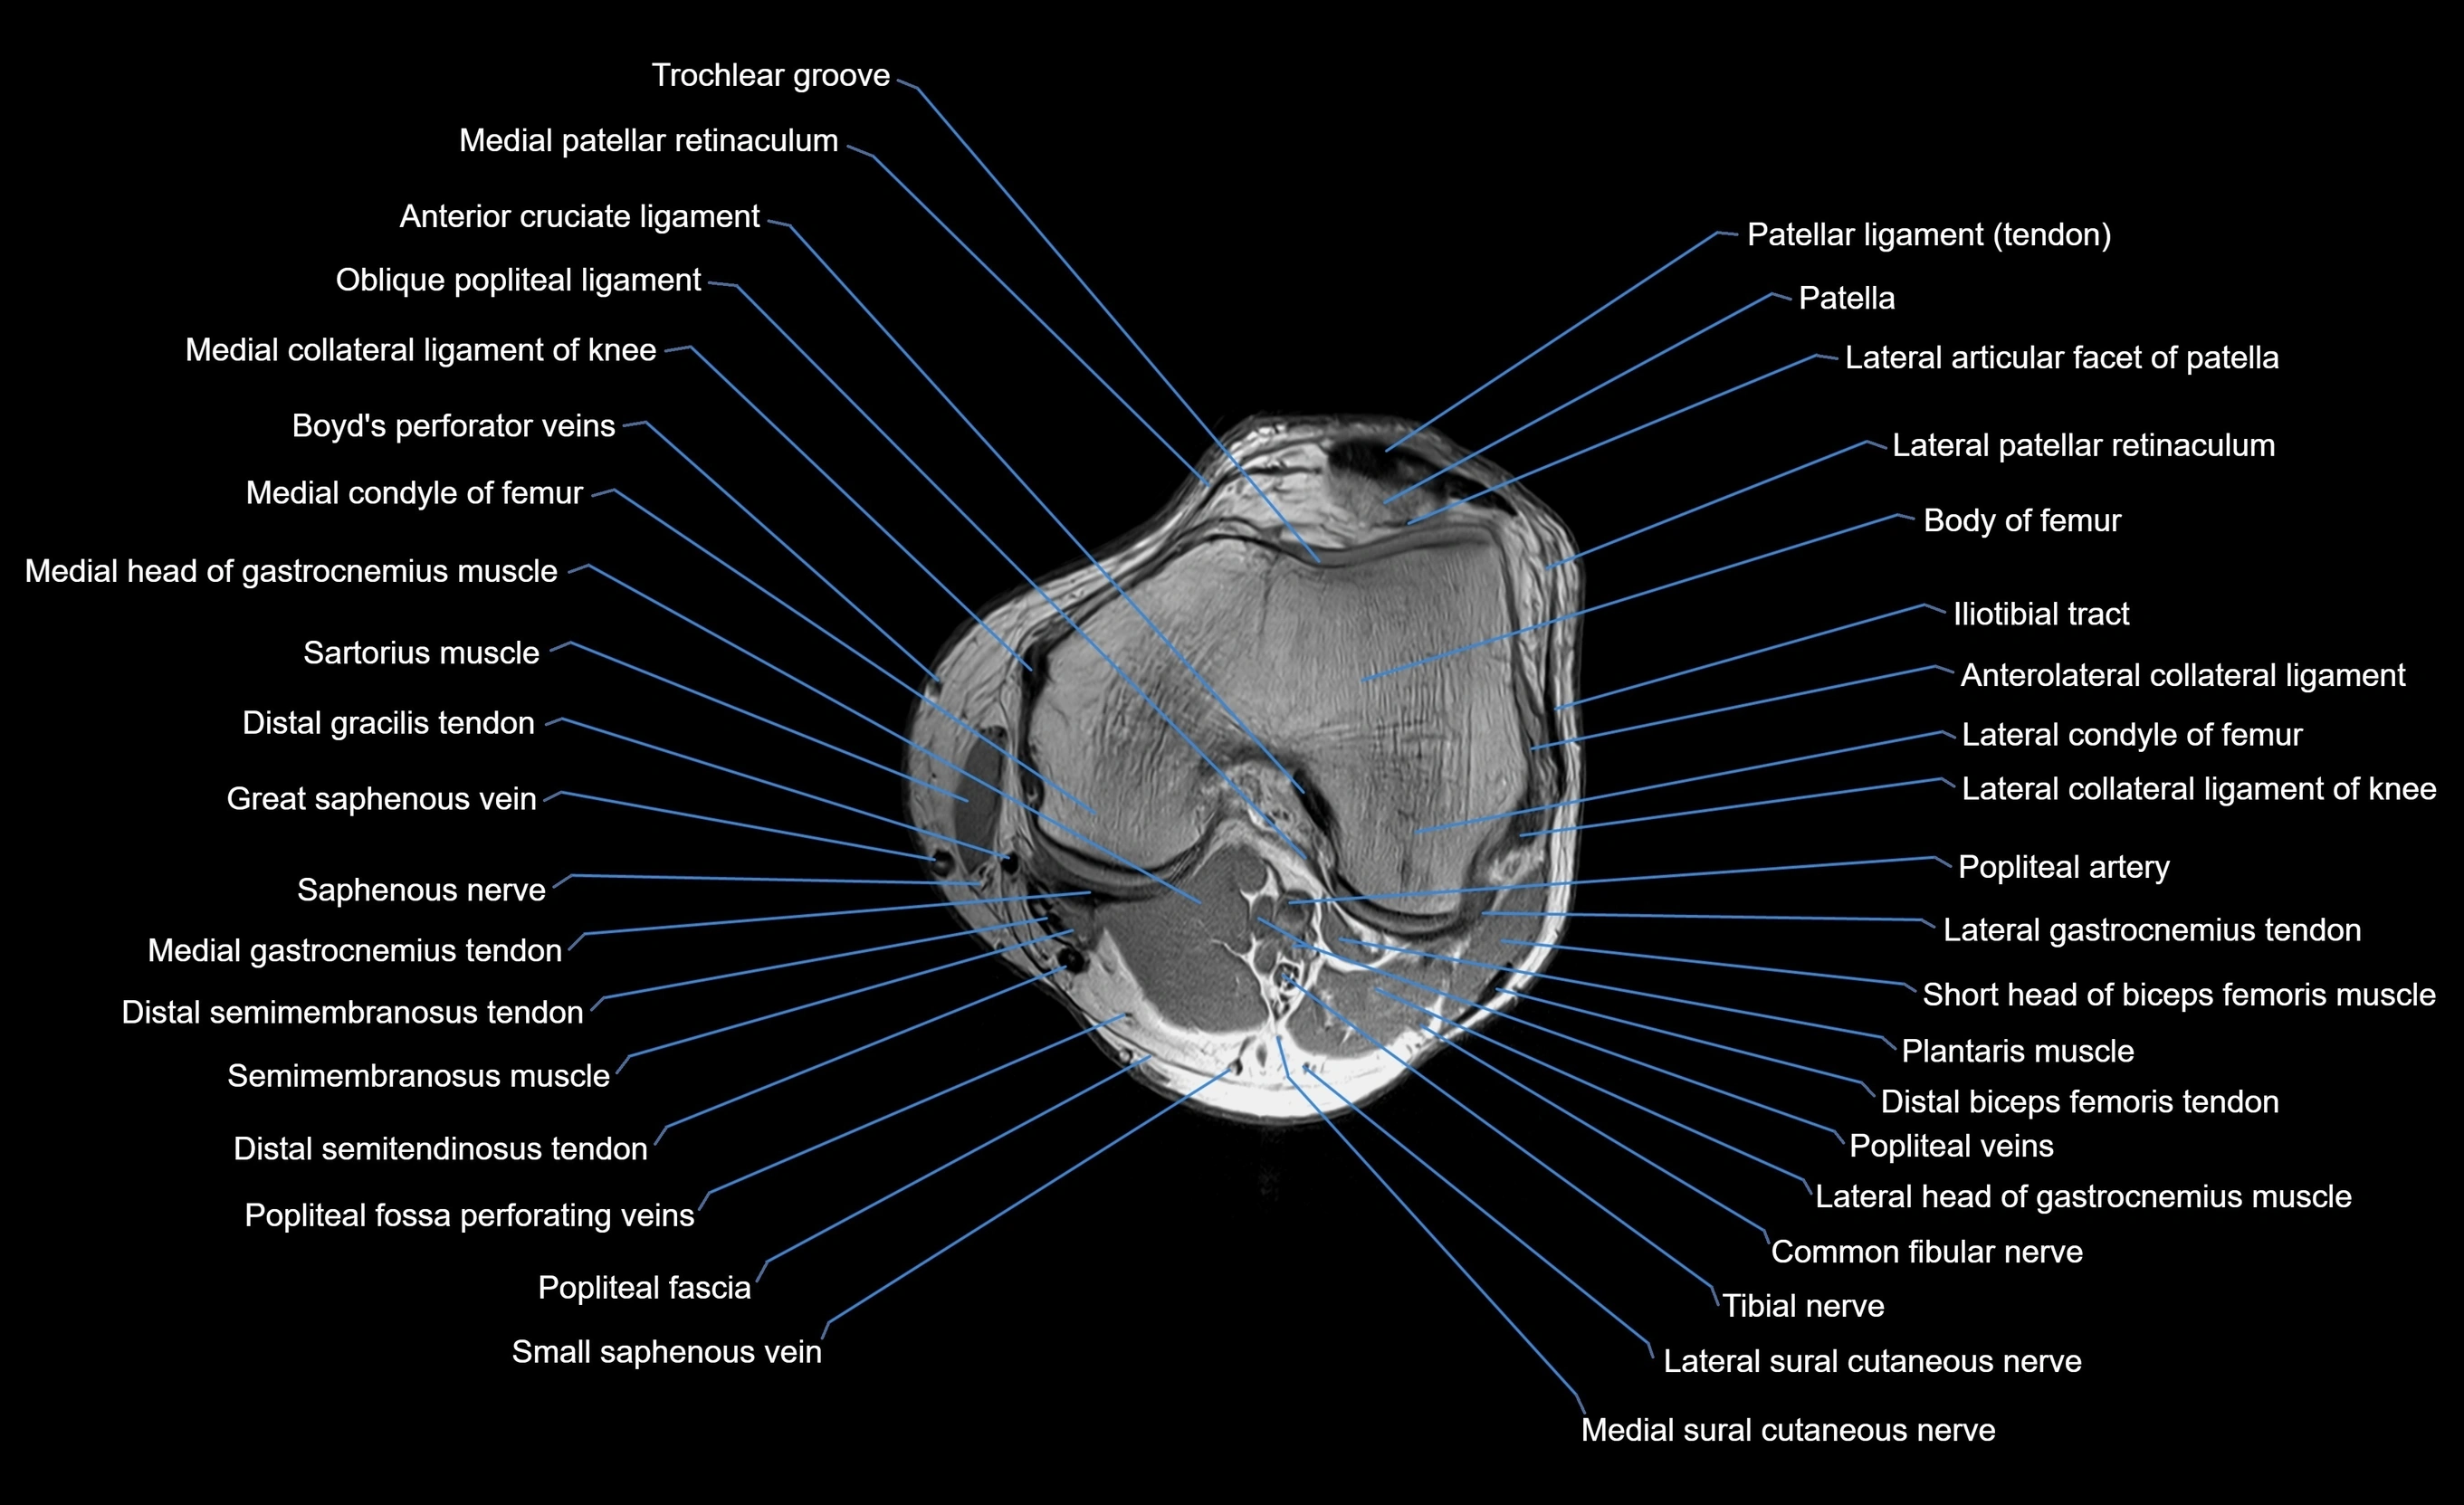

MRI image